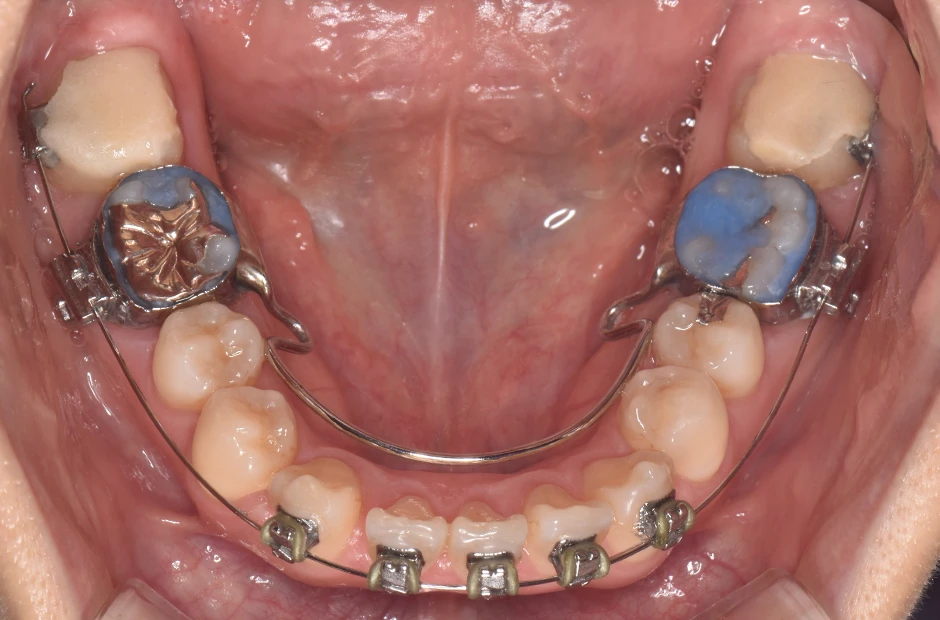

| 診断名・主訴 | 開咬 |

|---|---|

| 年齢・性別 | 23歳・女性 |

| 治療期間・回数 | 1年 12回 |

| 治療に用いた主な装置 | クワドヘリックス(QH)+タングガード → ロール付きリンガルアーチ |

| 抜歯部位 | 左右下8番 |

| 治療費 | 70万円(税抜) |

| リスク・副作用 | 装置による違和感・疼痛・歯肉退縮・歯根吸収・虫歯のリスクなど |

治療前

治療後